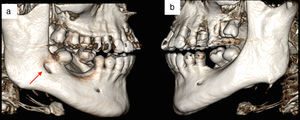

Case reportA 45-year-old Caucasian female patient was referred for a CBCT exam in order to evaluate jaw bone conditions prior to dental implant placement surgery. The scan was performed using an i-CAT Classic device t with 8cm×0.3 voxel size×20s of protocol scanning. During the evaluation of tomographic images using i-CAT Vision software (Imaging Science International, Hatfield, PA), an atypical IAN fenestration in the buccal right surface of the mandible was observed near the third molar, with 4.5mm of extension (Fig. 1). This anatomical variation was not observed on the left side. This IAN fenestration was a variation of the MC trajectory at the mandible buccal surface. There was no tomographic evidence of a MC bifurcation, no pathological process, and one exodontia 10 years ago. There was no other tomographic alteration.

Tridimensional reconstruction was produced with InVivo (Dental Anatomage, Version 5.1.10) in order to illustrate and improve the observation of the MC and adjacent structures (Fig. 2).